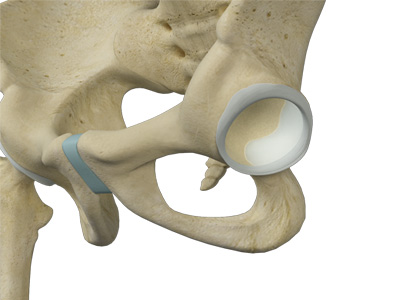

The hip joint is the junction where the hip joins the leg to the trunk of the body. It is comprised of two bones: the thigh bone or femur and the pelvis which is made up of three bones called ilium, ischium, and pubis. The ball of the hip joint is made by the femoral head while the socket is formed by the acetabulum. The Acetabulum is a deep, circular socket formed on the outer edge of the pelvis by the union of three bones: ilium, ischium, and pubis. The lower part of the ilium is attached by the pubis while the ischium is considerably behind the pubis. The stability of the hip is provided by the joint capsule or acetabulum and the muscles and ligaments which surround and support the hip joint.

The head of the femur rotates and glides within the acetabulum. A fibrocartilagenous lining called the labrum is attached to the acetabulum and further increases the depth of the socket.

Articular cartilage is the thin, tough, flexible, and slippery surface lubricated by synovial fluid that covers the weight-bearing bones of the body. It enables smooth movements of the bones and reduces friction.

- Acetabular labrum: The labrum is a fibrous cartilage ring which lines the acetabular socket. It deepens the cavity, increasing the stability and strength of the hip joint.